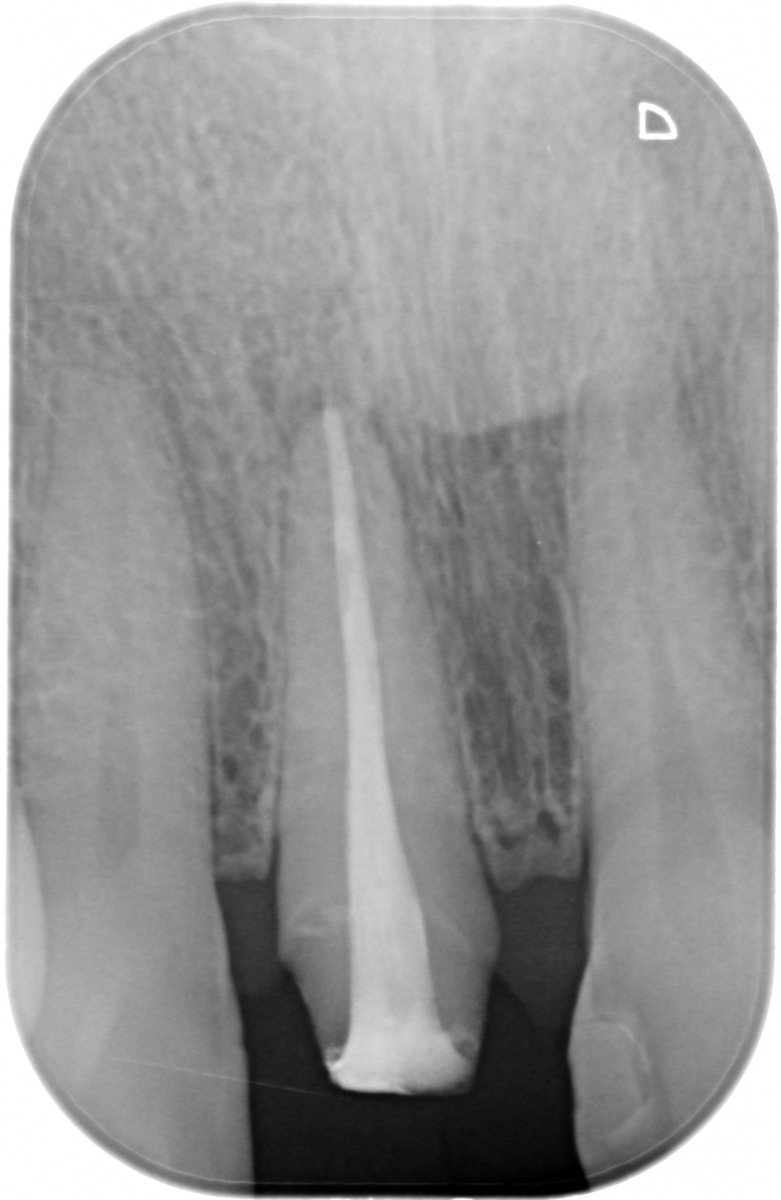

Il nostro Studio ha deciso di dotarsi di un sistema di radiografia digitale endorale con pellicole ai fosfori.

Una Scelta sofferta per la qualità forse ancora superiore dei formati in pellicola tradizionale, ma motivata dalle straordinarie prestazioni dello scanner di ultima generazione in dotazione all’apparecchio: legge e scarica sino ad 8 immagini per volta, le cancella e rende nuovamente e immediatamente riutilizzabili le pellicole ai fosfori.

I tempi di processazione delle immagini, inoltre, sono davvero molto rapidi: la singola radiografia è disponibile dopo appena 3-5 secondi mentre lo status endorale (13 fotografie endorali che vanno a comporre l’intera bocca) appare a monitor in solo 60 secondi.

• immagini ad alta risoluzione, comunque adempienti ad ogni requisito diagnostico;